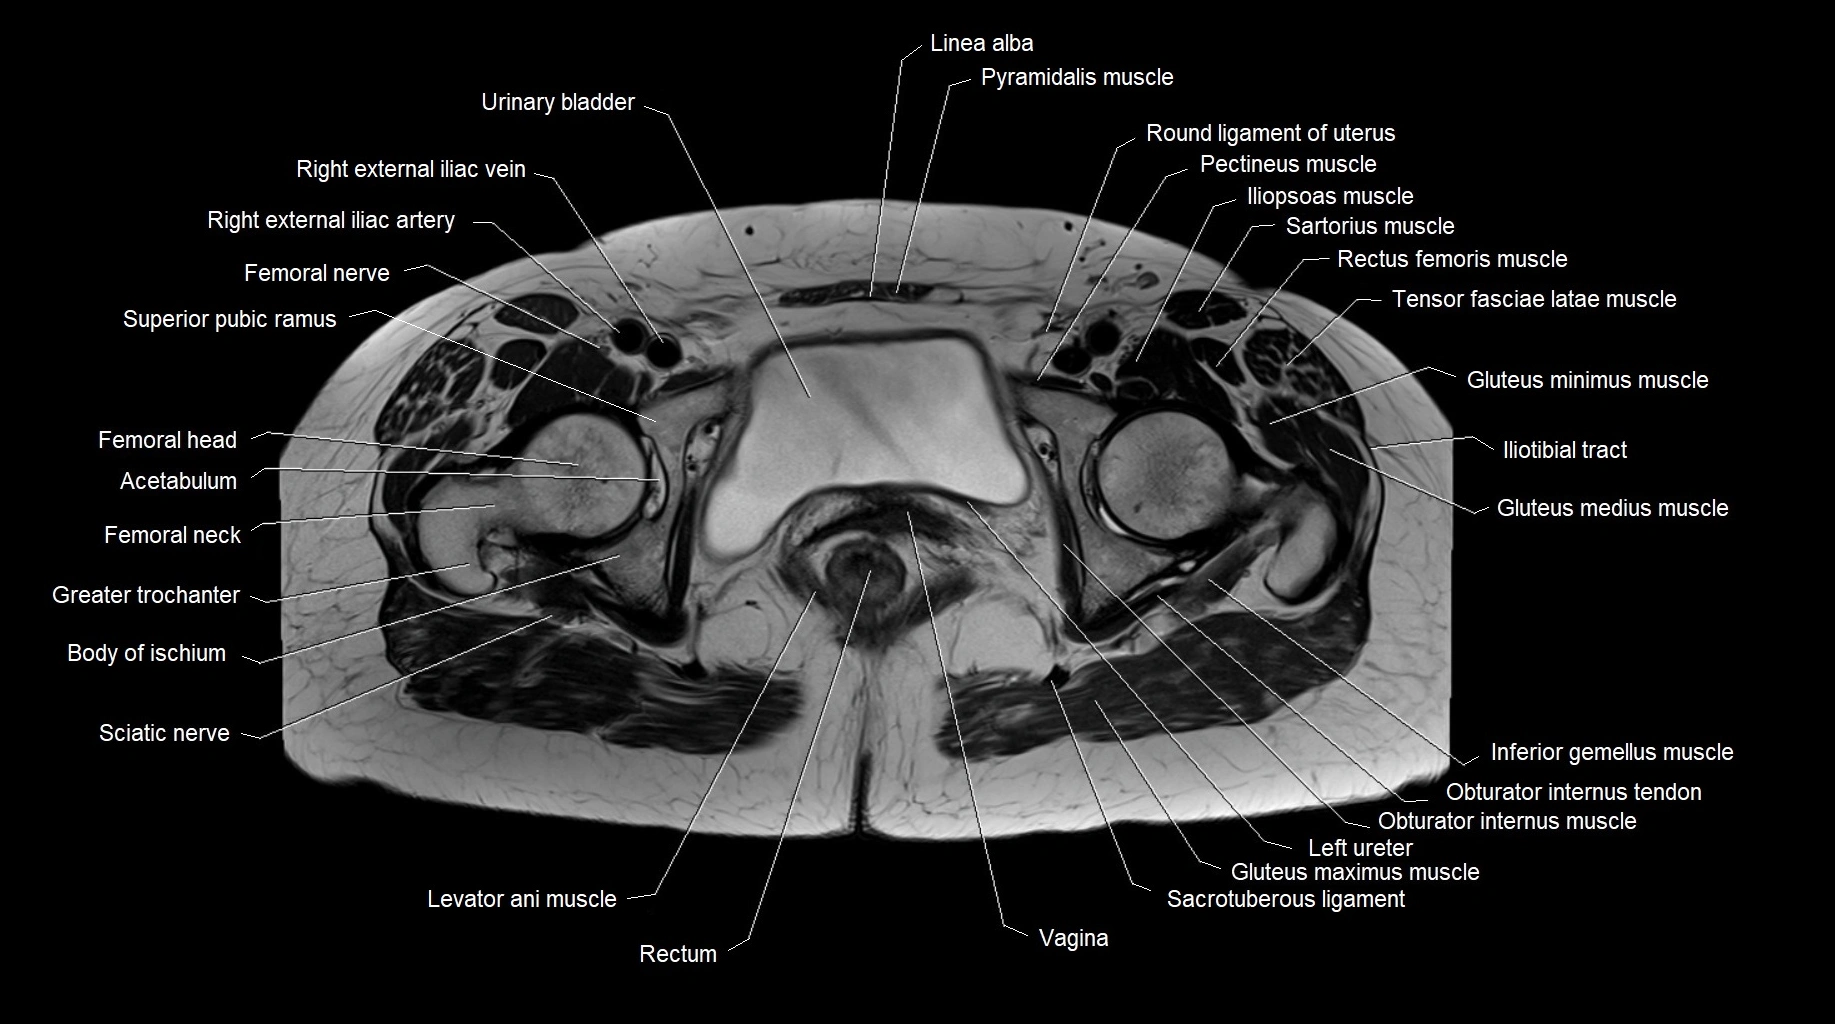

MRI images